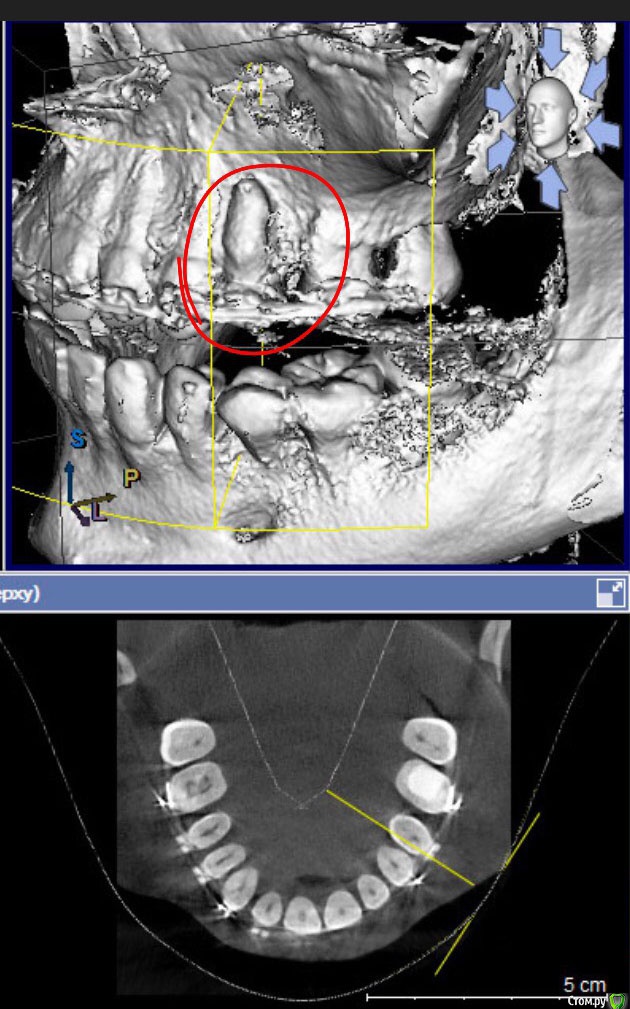

Селенга Опубликовано 14 апреля, 2017 Поделиться Опубликовано 14 апреля, 2017 Добрый день!Подскажите, пожалуйста, что делать в такой ситуации, проходила ортодонтическое лечение, как следствие корень вылез из кости, что в таком случае можно сделать? Этот зуб (см фото - верхний, беспокоит: реагирует на холодное, горячее и жевать практически невозможно) Мне это объяснял лечащий врач так, что костная ткань еще не наросла. Я не думаю, что она может нарасти!Какова вероятность лишиться зуба? Ссылка на комментарий

колесников Опубликовано 14 апреля, 2017 Поделиться Опубликовано 14 апреля, 2017 Здравствуйте! Можно попробовать сохранить зуб убрав с него нагрузку ,вывести из прикуса и заминировать. Перспективы туманные. Ссылка на комментарий